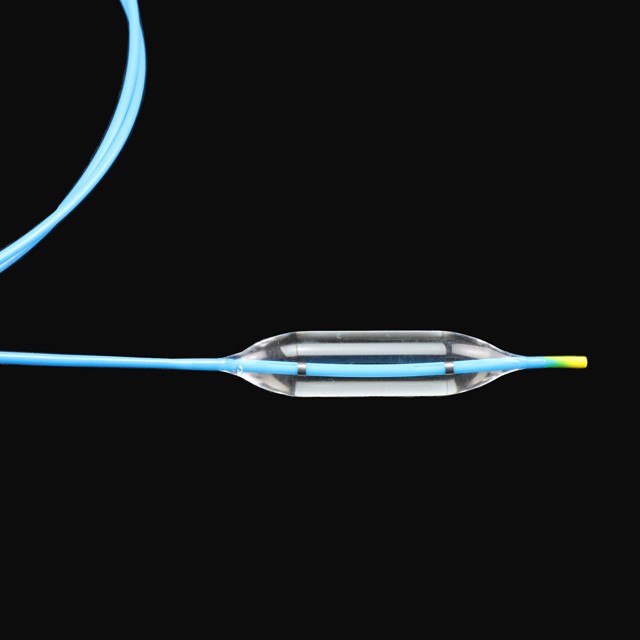

● idoneam adultis et adolescentes in DIATRUM operationem digestivorum tractu stricture sub endoscopes .

Characteres

● in Balloon potest esse gradual auctus ad tres distincta diametri sub propria pressura, providente multo magis choice pro medicis .

● elastica mollis consilium consilium, quod potest aequaliter intrare in scopum positus cum minus damnum .

● celeri INCILE Design adjuvat ad redigendum surgery tempus .

● Use Imported Material Cum High Press Resistentia et tutius Die .

● thermostatic shaping post multi-Wing Tueing confert ad optimum mollitiam et flexibilia receptum a working channel {I}}

● optimal consilio fistulam facit eam lenis et boni elasticitate, fortis torquens resistentia et facilius passability .

● radiopaque venalicium in utroque fines de Balloon potest providere precise positioning sub X Ray {{I}}

● Pre-input 0 {{II}} XXXV "Guide filum cum mollis tip et marcam, quae est facillimus estimate longitudinem in medio Guide filum.